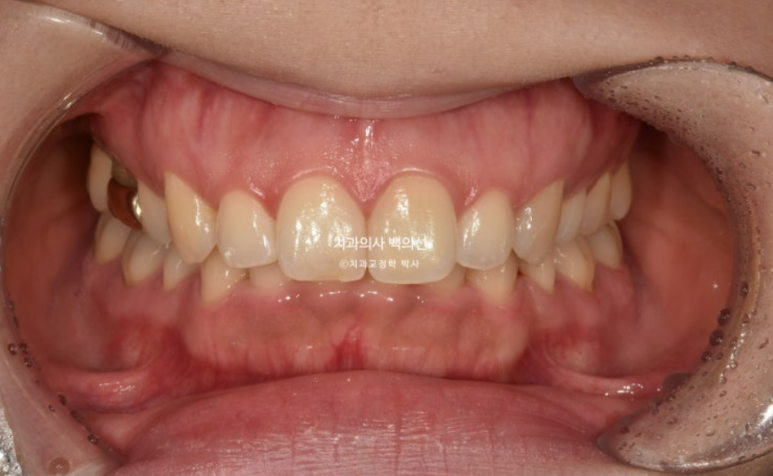

24.03

작년 3월 과개교합과 발치공간 벌어짐 때문에 재교정을 위해 찾아온 30대 환자분입니다.

아랫니가 안 보일 정도로 과개교합이 심합니다.